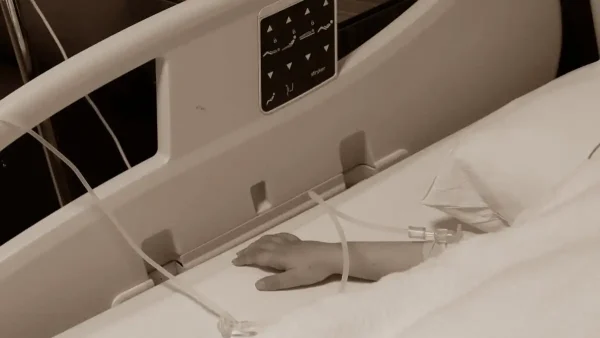

Το παιδί νοσηλευόταν στη ΜΕΘ Παίδων, μετά από μεταφορά από το Γενικό Νοσοκομείο Λεμεσού.

Σόκαρε τους πάντες η εικόνα του παιδιού που μεταφέρθηκε σκελετωμένο στο νοσοκομείο.